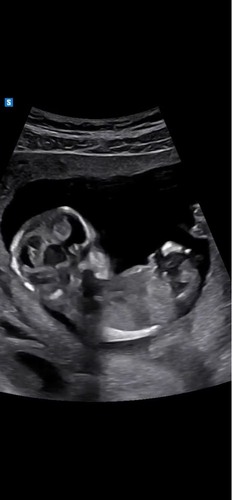

馃┓馃┑ wat denken julie

Hier zit helaas het beentje voor. Heb je meer foto鈥檚?